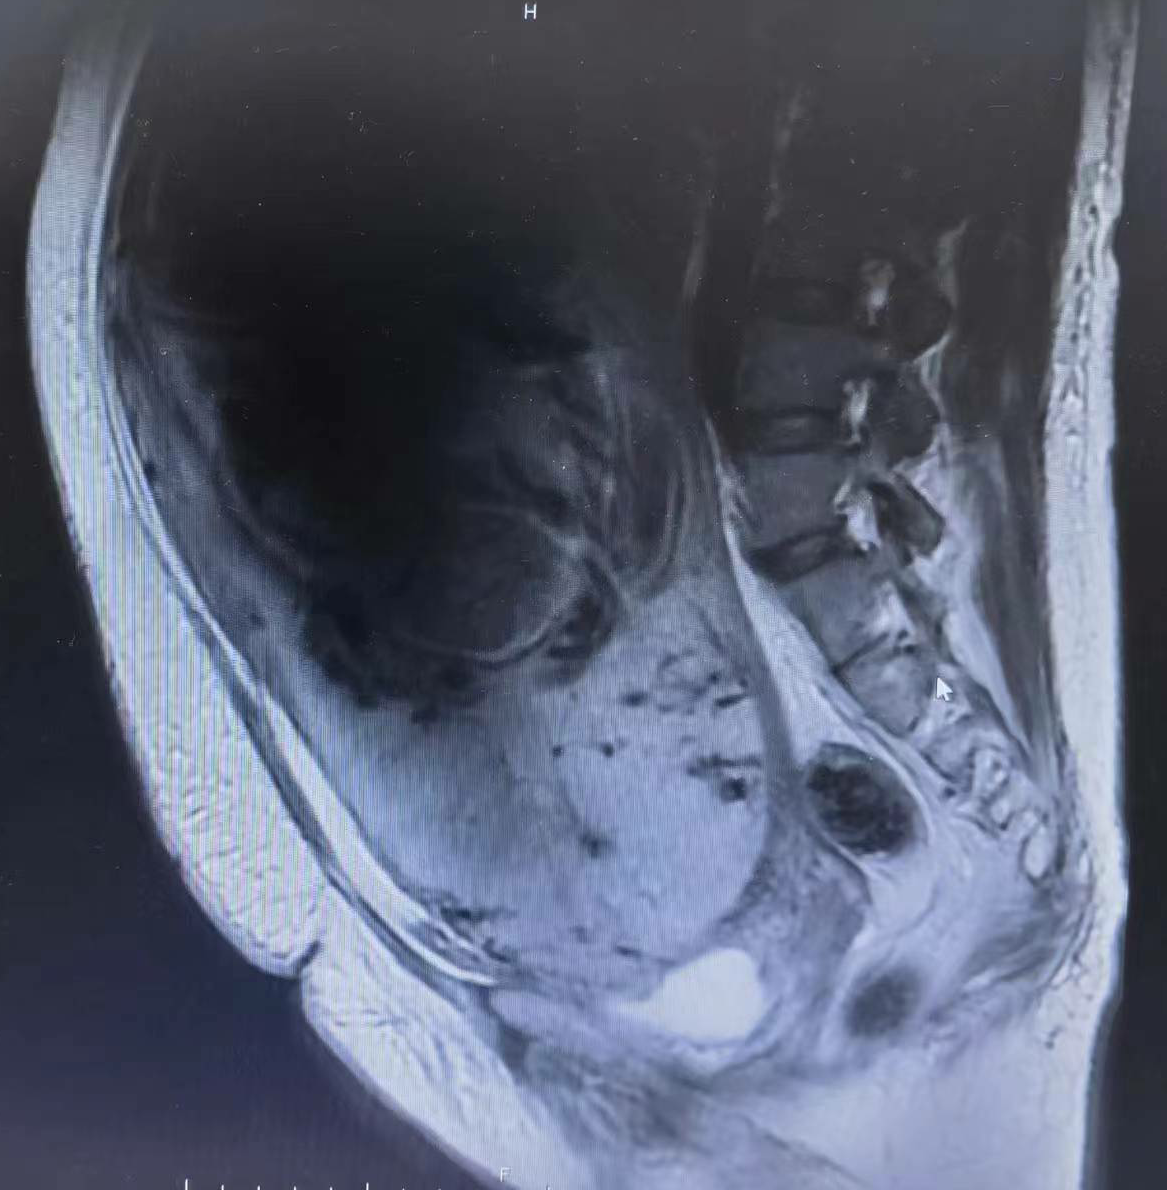

患者是一位44岁的高龄孕妇,曾经历过两次剖宫产手术,这是她的第三次怀孕。早在初期检查时就被诊断为切口疤痕妊娠,由于强烈的生育愿望,她没有接受医生关于终止妊娠的建议。

然而,在产前检查过程中,她并未察觉到完全性前置胎盘的迹象。直到晚期妊娠时,她被诊断为凶险性前置胎盘,我院妇产科的医疗团队考虑到凶险性前置胎盘可能引发严重出血和其他并发症,甚至有生命危险,但是孕妇的孕周尚小且无出血现象,决定让她住院保胎治疗,并尽力将胎儿保胎至孕足月。

新生儿复苏团队迅速采取措施进行抢救,在听到宝宝响亮的哭声那一刹那,在场的所有人都松了一口气。然而,接下来的挑战依然严峻,胎盘完全覆盖植入于宫颈口并穿透至临近脏器——膀胱,子宫收缩不良、粘连面和胎盘创面等多因素导致大量出血,为避免更严重的并发症,手术团队果断决定切除子宫。在所有医护人员的共同努力下,手术顺利结束。